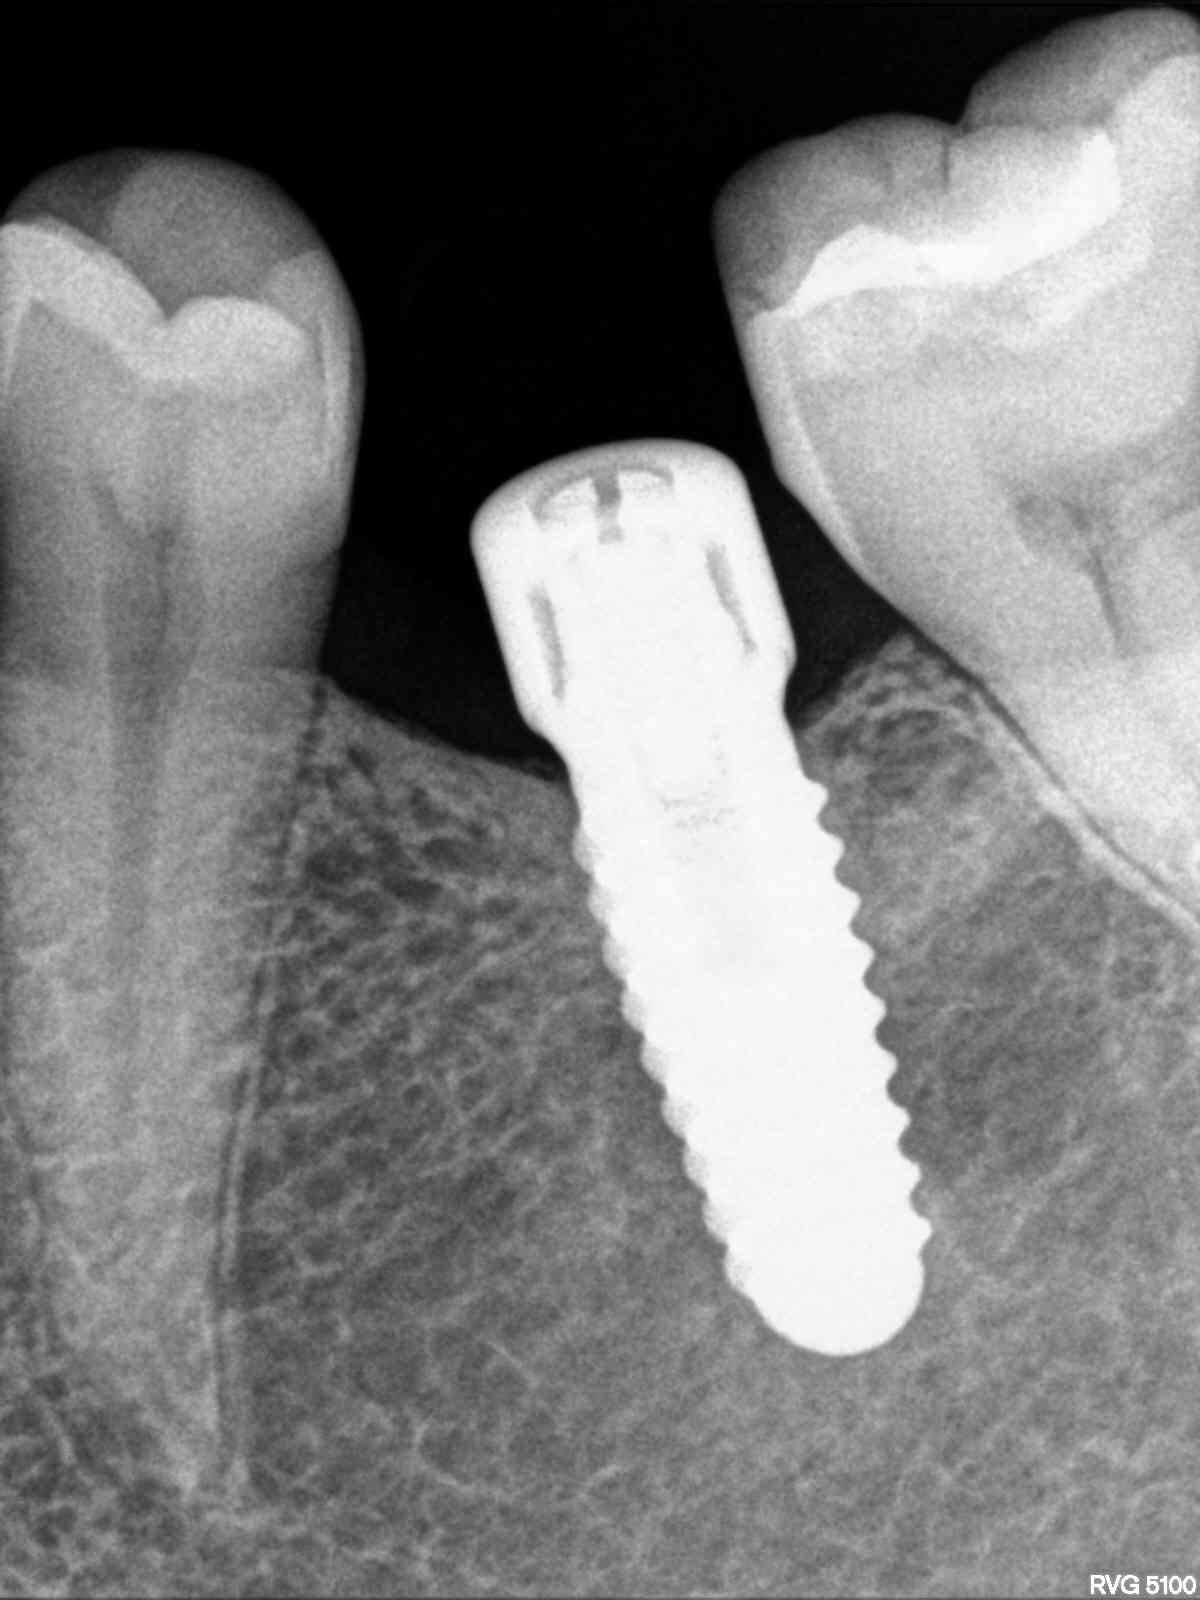

Implante 46 colocado hace 10 años

Paciente que acude con la corona en la mano y el implante tenía una parte del tornillo en la conexión, que aparece en la radiografía. La conexión del implante es [...]